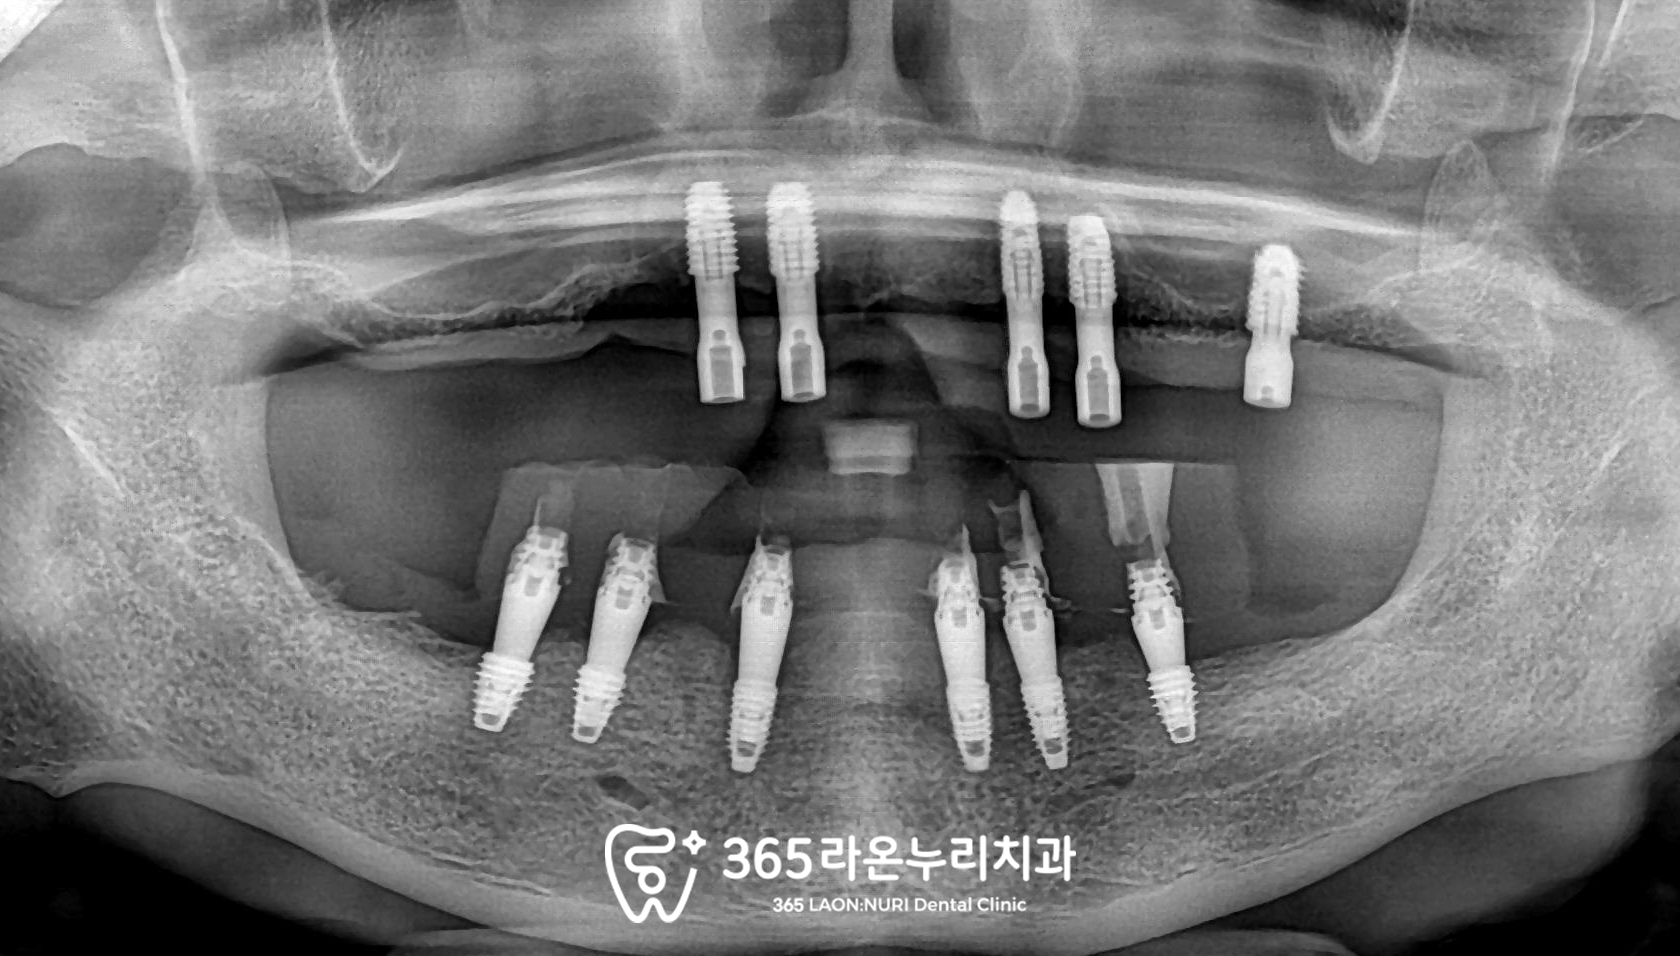

■ 3. 임플란트 식립

위턱뼈는 아래턱뼈에 비해

상대적으로 무른 성질을 갖고 있어

왼쪽 위 어금니 부근부터

픽스처를 심었습니다.

그 이후에 하악은

사전에 제작한 가이드를 이용하여

풀식립을 진행했습니다.

그리고 나면 수술 전 미리 디자인해둔

임시치아를 프린팅 하여

올려드리는데요,

어느 정도 잘 유지될 수 있도록

어버트먼트라는 연결지대주의 도움을 받아

이렇게 임시치아를 넣어드렸습니다.

■ 4. 최종 보철 수복

치아 없이 오래 지내셔서

하루라도 빨리 저작하실 수 있게

최종 보철을 만들고 있는 모습입니다.

위아래 앞니의 가운데 선(정중선)을

고려하여 하악 all on X를

제작하였으며

그간 불편감을 최소화하기 위해

임시치아를 끼면서 적응도 많이 하셨기에

마지막 장착 날에는

큰 교합조정 없이

편안하게 안착되었습니다.